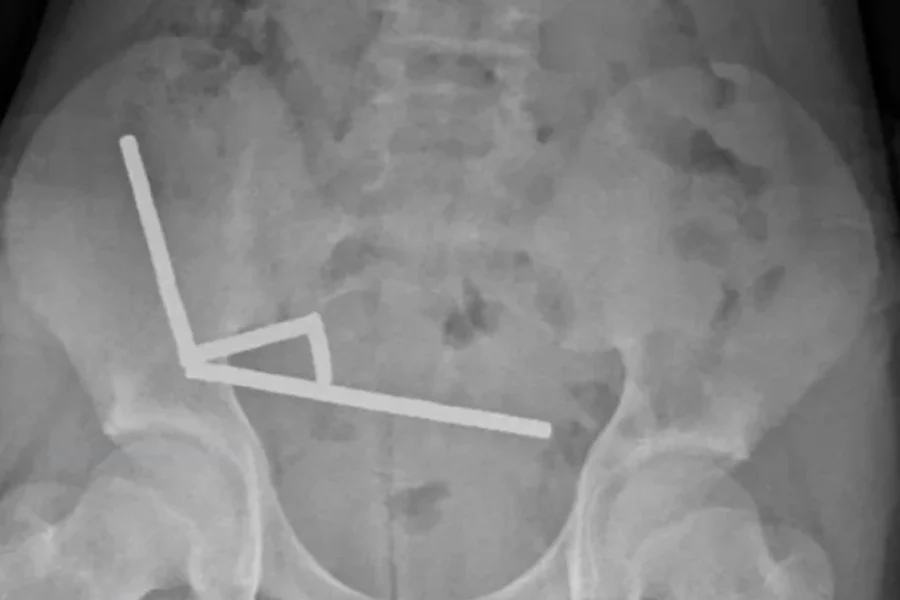

Η ακτινογραφία έδειξε ότι οι μαγνήτες είχαν συσσωρευτεί σε τέσσερις ευθείες γραμμές μέσα στα έντερα του παιδιού. Βρίσκονταν σε ξεχωριστά μέρη του εντέρου και είχαν κολλήσει μεταξύ τους λόγω μαγνητικών δυνάμεων.

Οι γιατροί ανέφεραν ότι η πίεση των μαγνητών είχε προκαλέσει νέκρωση σε τέσσερα σημεία του λεπτού εντέρου και του τυφλού εντέρου του αγοριού, το οποίο αποτελεί μέρος του παχέος εντέρου. Οι χειρουργοί επενέβησαν για να αφαιρέσουν τον νεκρό ιστό και να ανακτήσουν τους μαγνήτες.